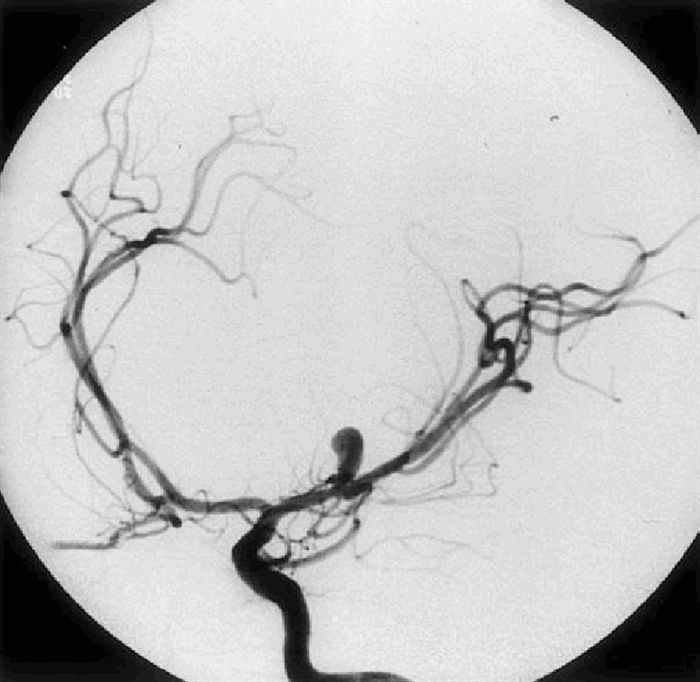

- Ангиография - позволяет точно определить локализацию и степень поражения сосудов. С помощью ангиографии можно определить необходимо ли оперативное устранение аневризмы или можно обойтись консервативным лечением. Недостатком этого вида исследования считается высокая сложность проведения манипуляций. При введении контраста в кровь возможны аллергические реакции. Выявленная аневризма – это "мина замедленного действия", которая рано или поздно, но обязательно приведет к разрыву сосуда и субарахноидальному или внутримозговому кровоизлиянию (геморрагическому инсульту). Если своевременно не провести хирургическое лечение, последствия аневризмы могут быть катастрофическими.

Аневризмы внутричерепных сосудов чаще всего располагаются на основании мозга. Но не исключено и поражение более мелких артерий на поверхности больших полушарий или в толще мозговой ткани. Выделяют аневризмы внутренней сонной артерии, средней мозговой, передней мозговой и соединительной артерий, сосудов вертебробазилярного бассейна (Виллизиева круга). В некоторых случаях отмечается наличие симметричных дефектов.

- аневризмы в передней соединительной артерии составляет 20-30% всех диагностированных случаев;

- аневризмы средней мозговой артерии и бифуркации внутренней сонной артерии - 5-20% всех случаев;

- аневризмы внутренней сонной артерии - 3-15% всех случаев.